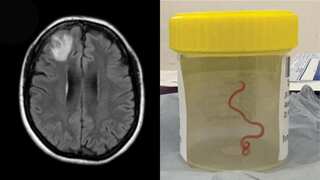

From snakes to humans: Live parasitic roundworm discovered in Australian woman's brain